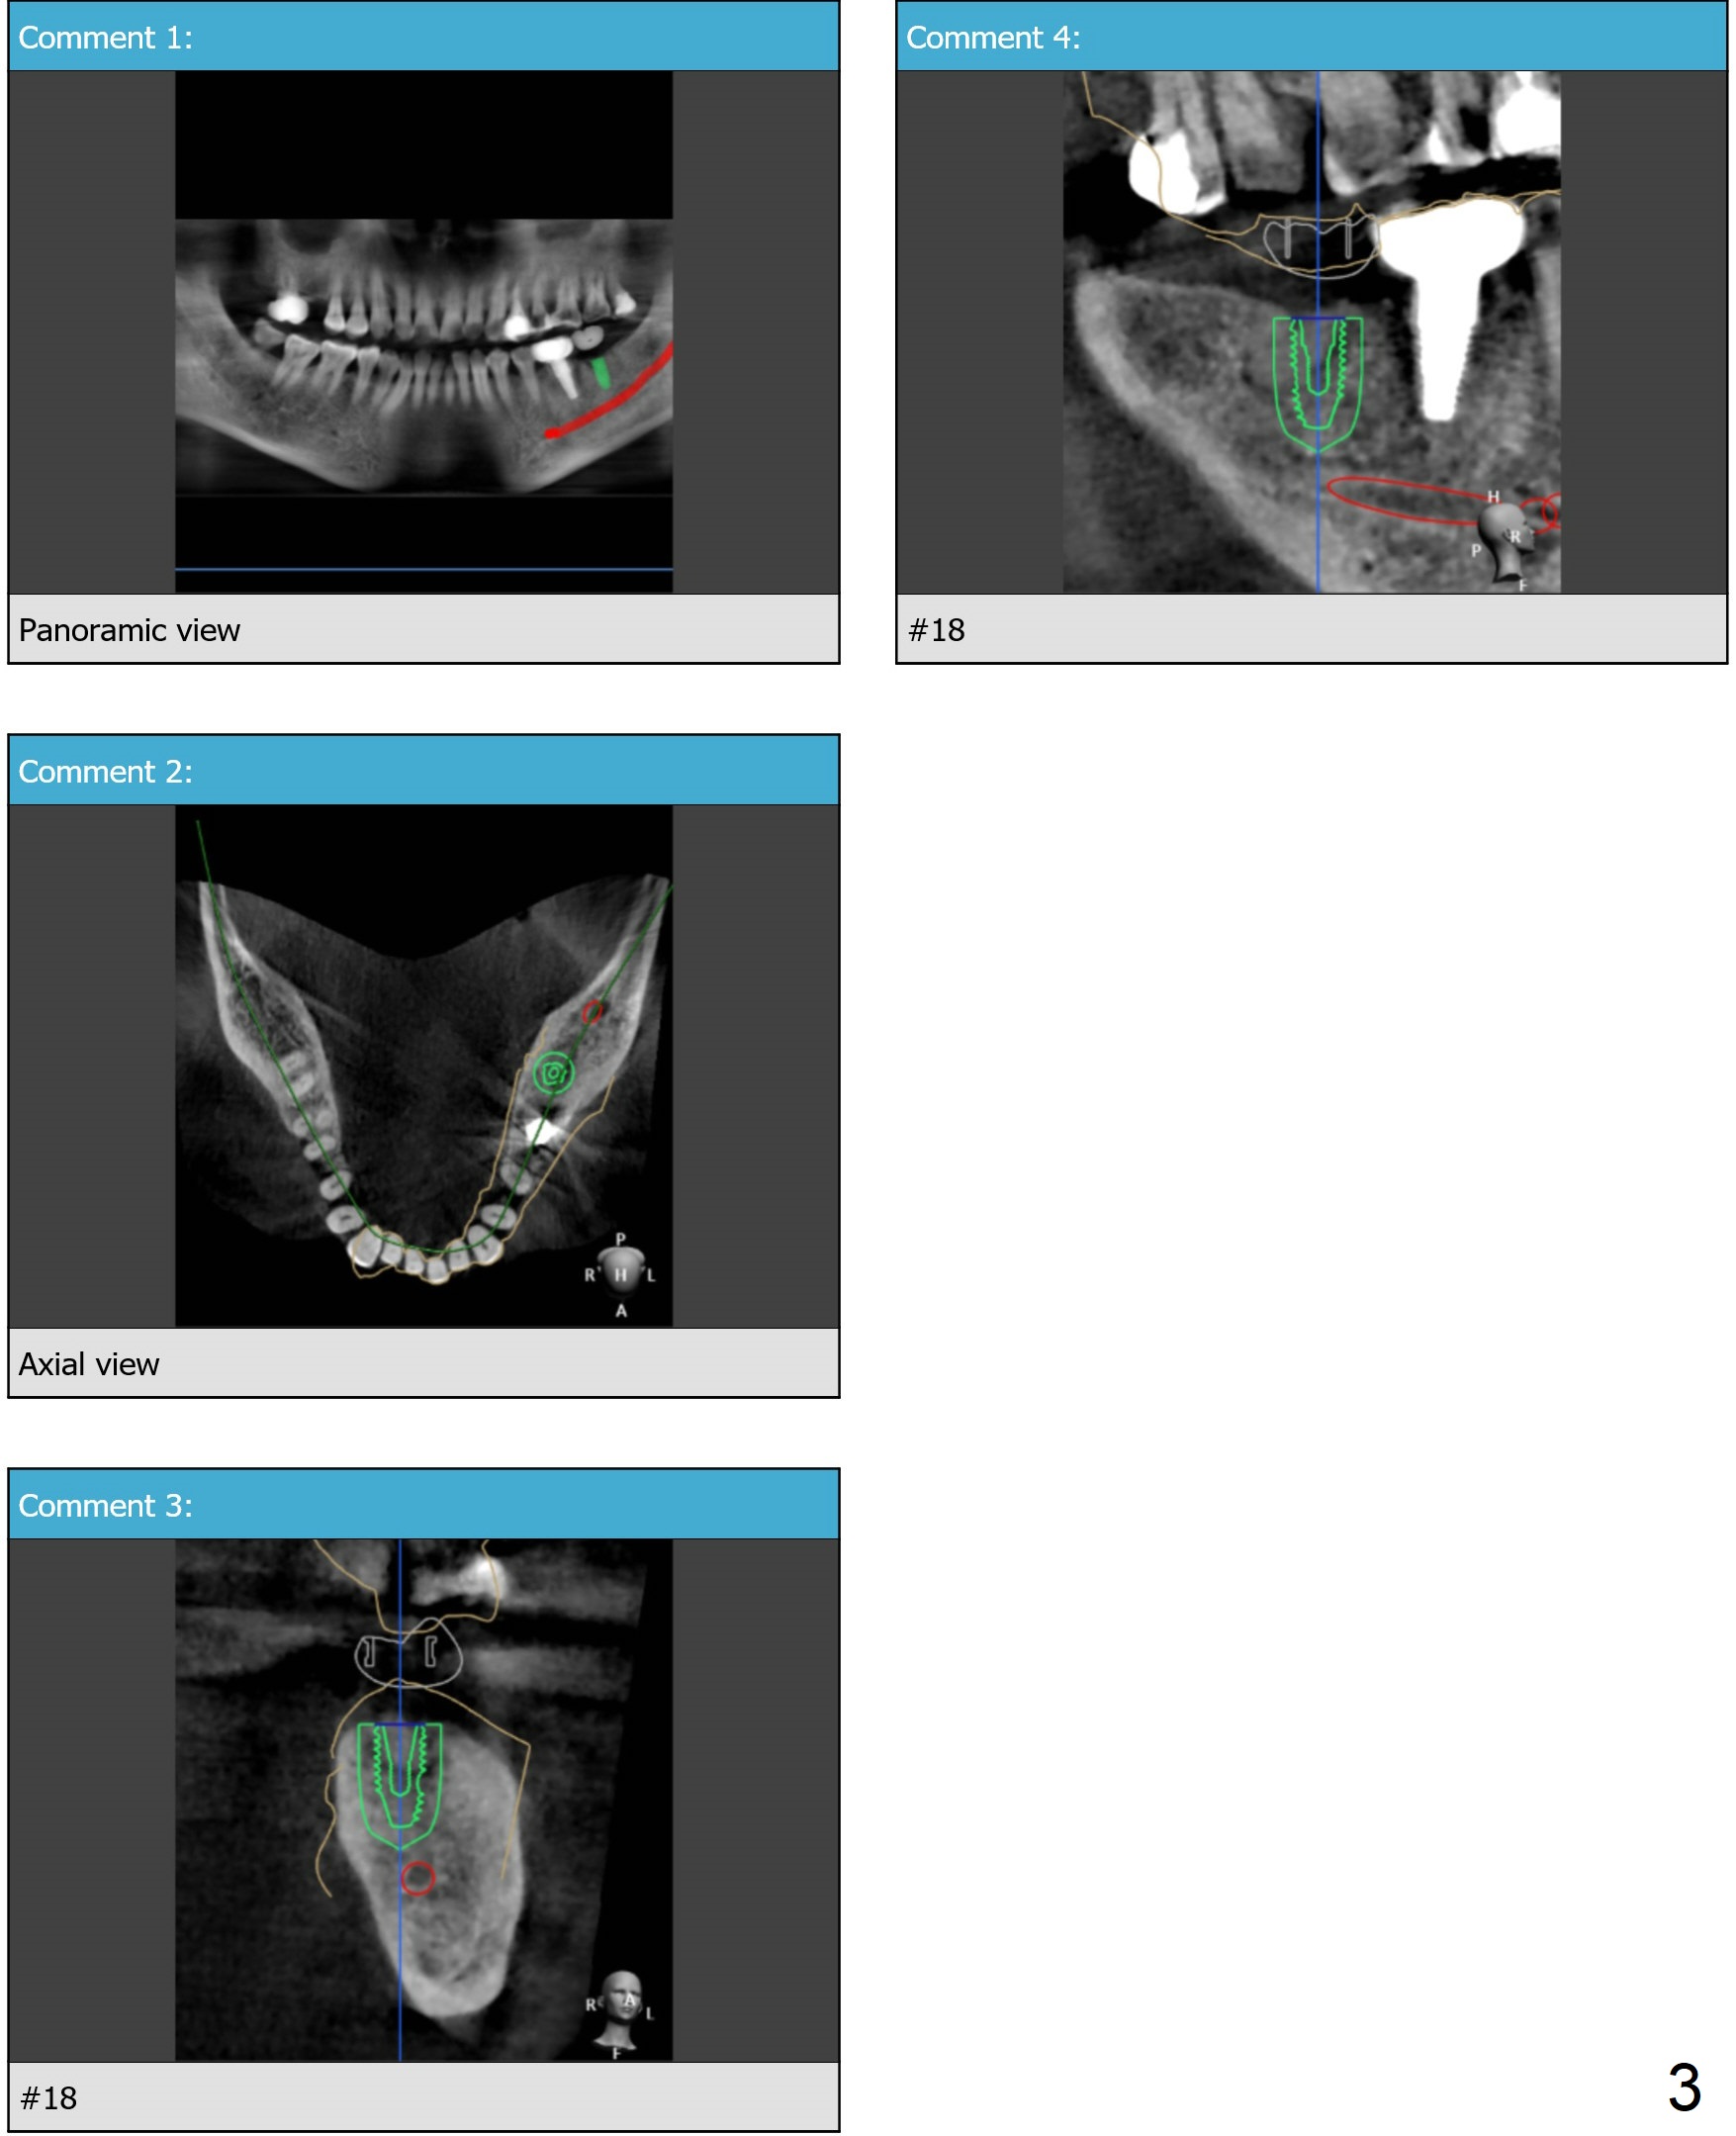

Guide Design 7 Months Post Socket Preservation

Return to Lower Molar Immediate Implant, Armaments, Depth Control

Xin Wei, DDS, PhD, MS 1st edition 06/11/2018, last revision 04/14/2019